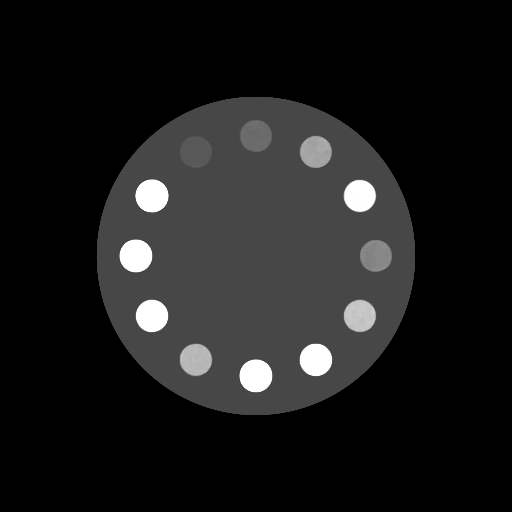

(30-cm cylindrical phantom)